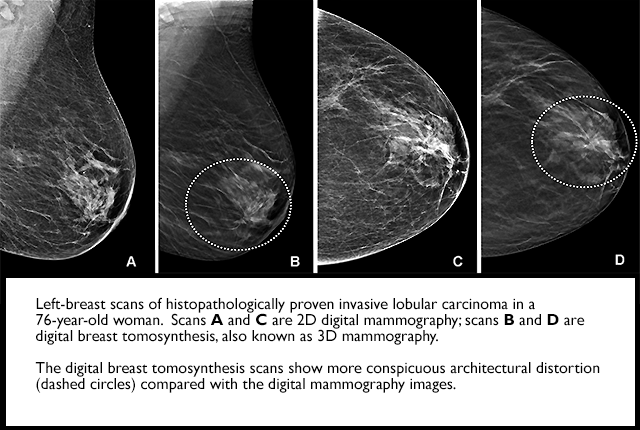

Researchers have found that digital breast tomosynthesis (DBT) has improved breast-cancer screening performance in community practice and identifies more invasive cancers, compared with digital mammography. In addition, radiologists’ interpretive performance has improved with DBT.

Compared with BCSC digital mammography screening exams from the same time period and previously published BCSC and National Mammography Database performance benchmarks, all performance measures were higher for DBT except sensitivity and false-negative rate, which were similar to concurrent and prior digital mammography performance measures.